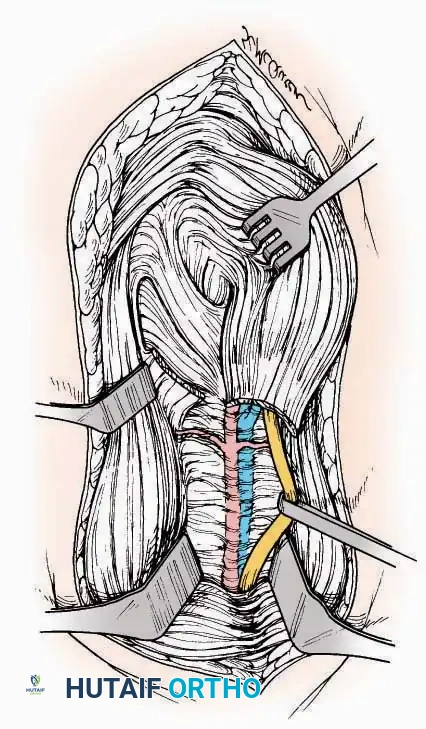

* Internervous Plane: The deep dissection exploits the plane between the Extensor Hallucis Longus (EHL) tendon (innervated by the deep peroneal nerve) and the Extensor Digitorum Longus (EDL) tendons (also innervated by the deep peroneal nerve).

* Neurovascular Bundle: Incise the extensor retinaculum. Carefully identify the anterior tibial artery and the deep peroneal nerve, which typically lie between the EHL and EDL, or directly deep to the EHL. Retract the neurovascular bundle laterally with the EDL, or medially with the EHL, depending on the specific anatomical variant encountered (lateral retraction is most common).

* Capsulotomy: Incise the anterior joint capsule longitudinally. Elevate the capsule subperiosteally from the anterior tibia and the talar neck to expose the entire tibiotalar articulation.